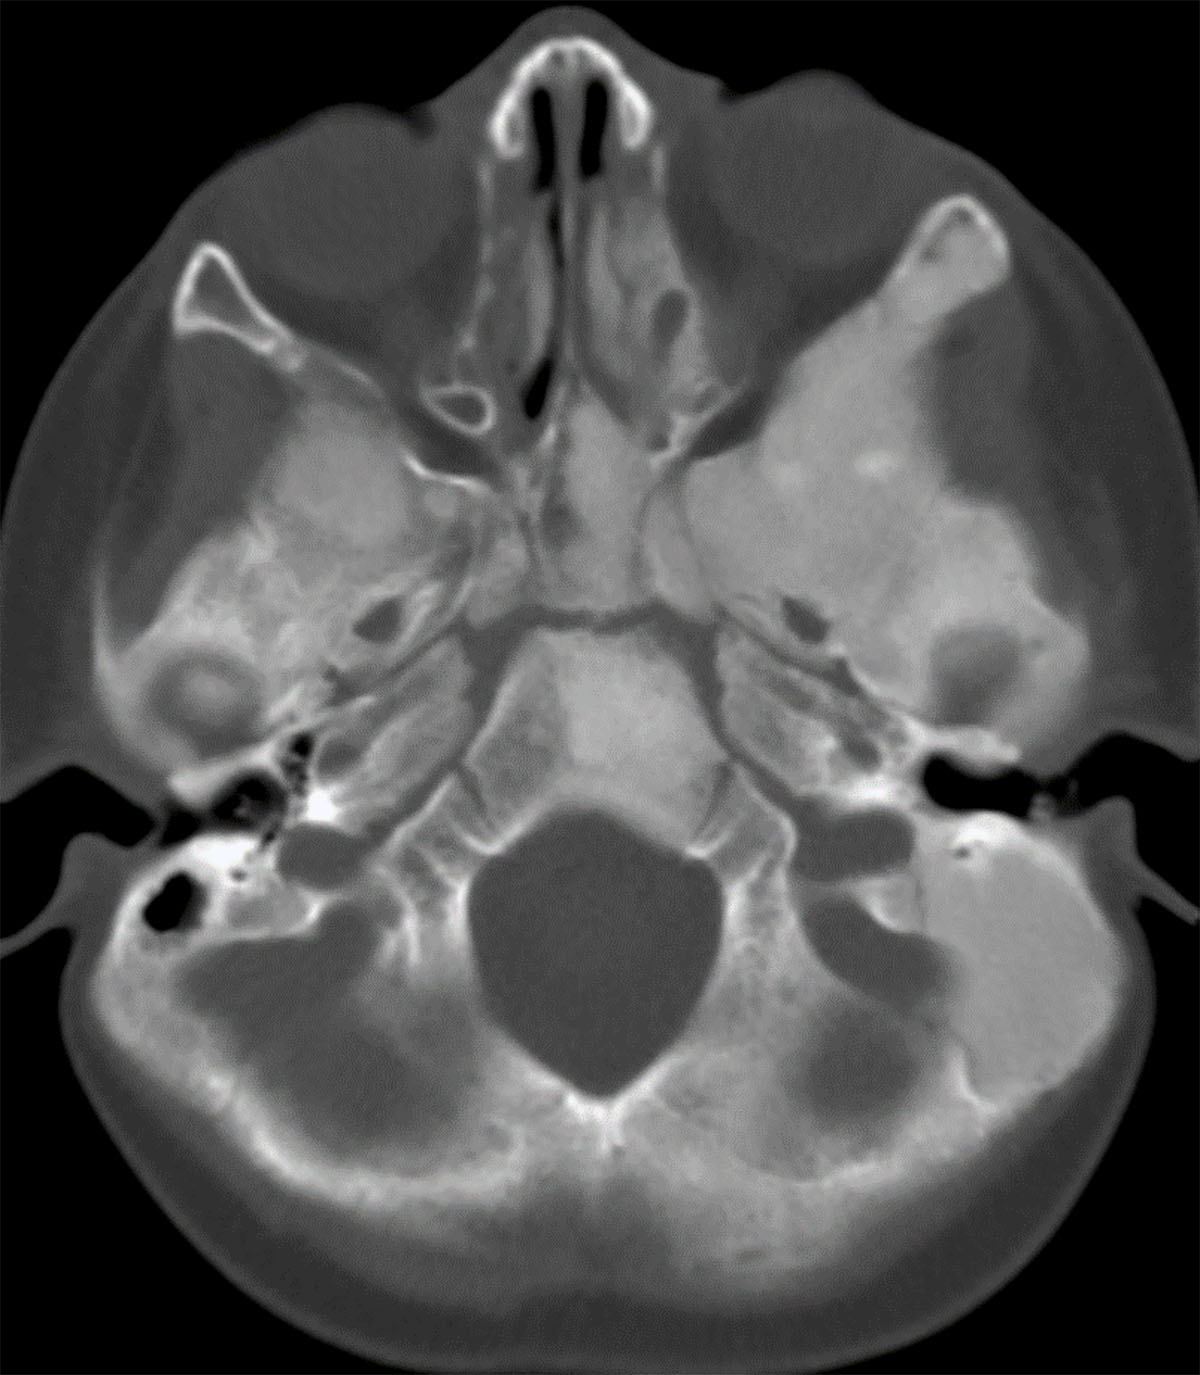

Figure 1

Fibrous dysplasia in McCune-Albright syndrome. On this axial CT image in bone window settings, extensive ground glass appearance and osseous expansion is seen, typical of fibrous dysplasia.